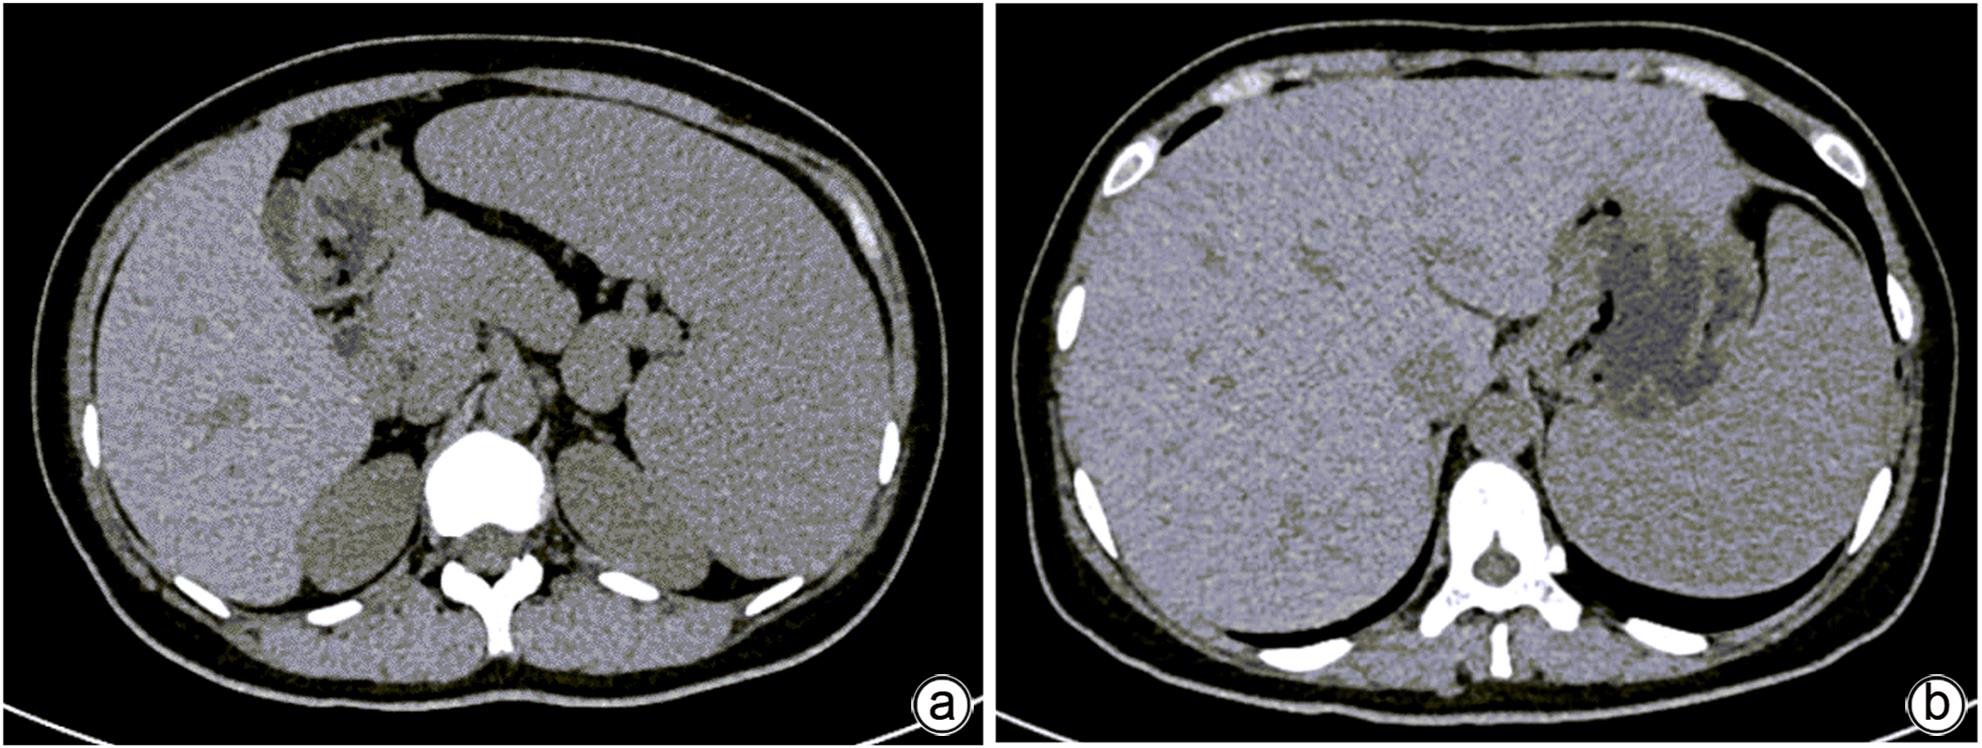

胰腺内副脾误诊2例报告

摘要(1364) HTML (331) PDF (1188KB)(158)

副脾是指正常脾脏以外存在的,与主脾结构相似,有一定功能的脾脏组织,其中完全被胰腺包裹的胰腺内副脾(IPAS)发生率仅为2%,因其临床症状不典型,影像学特征与胰腺神经内分泌肿瘤、胰腺实性假乳头状瘤以及其他胰腺占位性病变较为相似,临床上容易误诊。本文报道了2例分别被误诊为胰腺神经内分泌肿瘤和胰腺实性假乳头状瘤的IPAS患者,并分析误诊原因,总结诊疗经验,以期提升临床对IPAS明确鉴别诊断的认识。